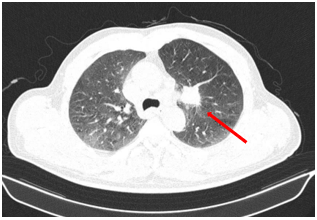

Bệnh nhân được chụp cộng hưởng từ sọ não, phát hiện khối u vùng trán phải, kích thước 17 x 20 mm gây phù não rộng xung quanh theo dõi tổn thương thứ phát

Hình 1

. Hình ảnh cộng hưởng từ sọ não ngày 25 tháng 03 năm 2025 (hình bên trái: xung T1; hình bên phải: xung T2) cho thấy khối u não vùng trán phải (mũi tên).